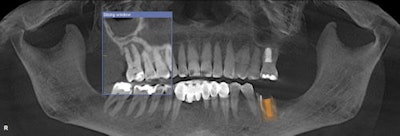

The CBCT images were impressive and became the foundation for my complete dental examination. Incidentalomas were numerous: multiple periapical pathologies and moderate to severe periodontal disease. Although he presented for his maxillary incisor, I was able to capture his attention and devise a pragmatic plan to improve the overall prognosis for his entire dentition.

A challenging road lay ahead as multiple disciplines of dentistry would be necessary to return a poorly maintained dentition to a healthy fully functioning one. Note that multiple asymptomatic periapical lesions existed with #3, #12, #13; multiple teeth were missing; and there was generalized severe periodontal breakdown.